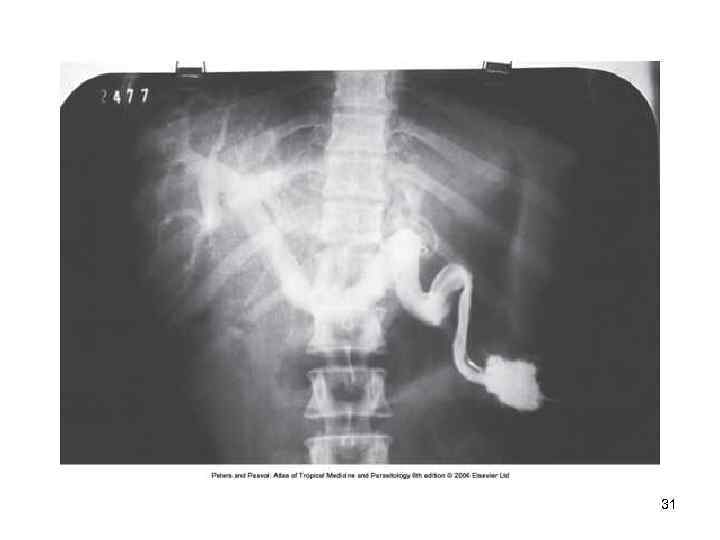

32

Диагностика • Исследование мочи на яйца шистосом после центрифугирования • Максимальное количество яиц выделяется с мочой около 10 -12 часов дня • Интенсивная инвазия оценивается при числе яиц более 50 на 10 мл. мочи • Цистоскопия позволяет выявить изменения на слизистой оболочке мочевого пузыря: гранулемы, » песчаные пятна» . • Эндобиопсия- выявляются яйца S. haematobium • Обзорная рентгенография –обнаруживается обызвествление стенок мочевого пузыря Контрастная урография -изменение структуры мочеточников 33